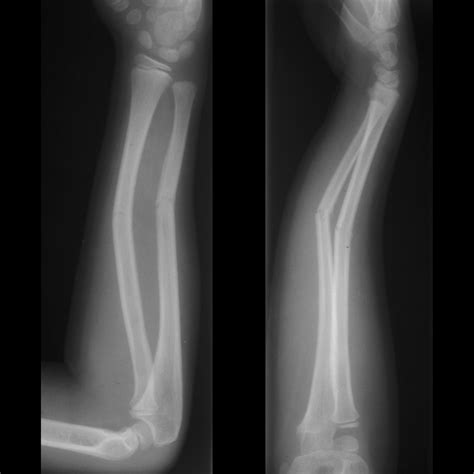

Diagnosing Acute Fractures

Diagnosing an acute fracture involves several steps to determine the extent and type of injury. The process typically includes:

• Imaging Tests: X-rays are the primary tool for diagnosing fractures. In some cases, CT scans or MRIs may be used for more detailed images.

Imaging tests are crucial for understanding the acute fracture meaning and planning the appropriate treatment. X-rays provide clear images of the bone structure, helping to identify the type and severity of the fracture.